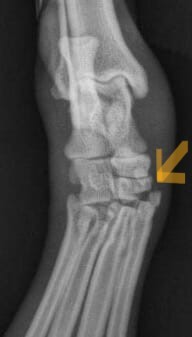

Mild cases will have swelling of the affected joint on palpation and discomfort with manipulation. Moderate to severe cases can have a visible loss of the upright carriage of the wrist or ankle with palpable instability. X-rays will show soft tissue swelling around the affected joint. The joints will ‘open up’ when pressure is placed to test the areas of concern. It is very important to identify at what level within the wrist or ankle the damage is present and if there is an associated fracture because this can change what procedure is recommended.

X-rays will demonstrate the soft tissue swelling. The instability can also be demonstrated with stressed views. In severe cases, a complete luxation may be present.